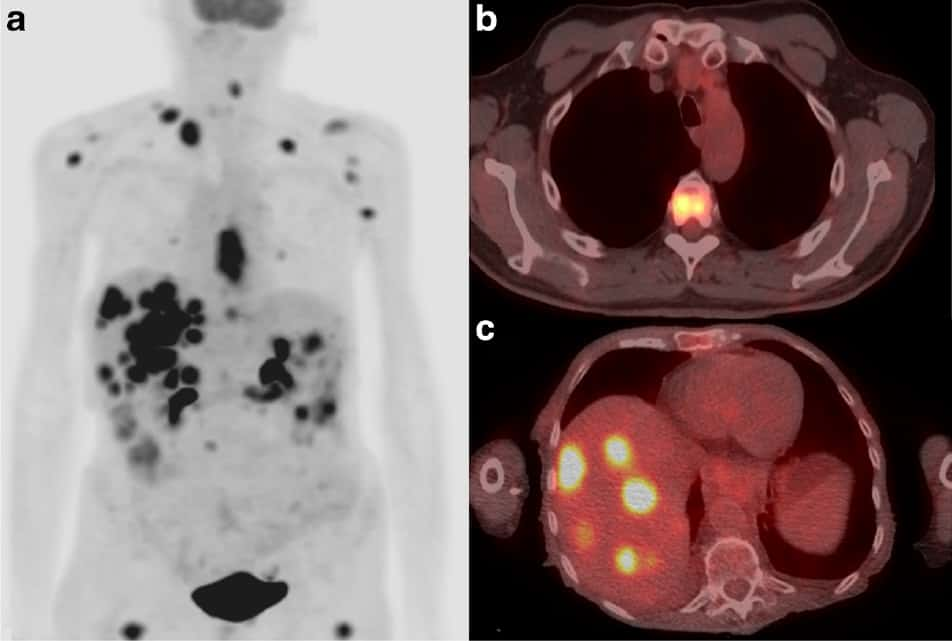

The problem with raising insulin is that it is insulin that delivers sugar to the cells, including to cancer.  When sugar is consumed, and then enters the blood, the β-cells of the pancreas release insulin.  This insulin travels throughout the body to promote the entry and storage of glucose in cells all over the body.  Cancer takes so much more glucose than normal cells that you can actually see the rough outline of how much more on a PET scan.  In a PET scan, radioactive glucose is injected into the body, and it goes to the cancer with such strong affinity, and then is picked up by the camera of the PET scan that you see nearly black-and-white differences showing where the sugar goes.

The bright spots in the following image show cancerous tumors, where sugar was taken up avidly in the liver.  In stark contrast, the surrounding red areas are normal tissue.  It was sugar, delivered by insulin, that found the difference between the two types of tissue in the following photograph.

PET / CT scan. Eur. J. Nucl. Med. Mol. Imaging 45 1742